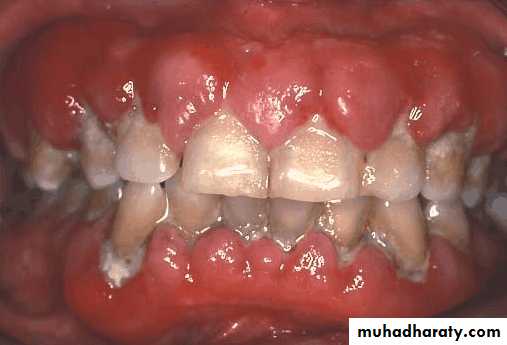

• Presence of large number of restored teeth, signs of recurrent caries, the evidence of decalcification – susceptible to caries

• Unless an exceptional level of plaque control can be achieved, the prognosis for the treatment is poor.

• The placement of crowns on the abutment teeth may be indicated if the patient is highly susceptible to caries.

Evaluation of caries susceptibility